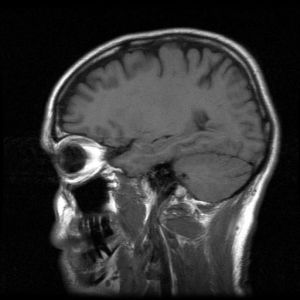

3. 3D Image

| MRI scan of a human head |

Image taken from mesotheliomasymptoms.com